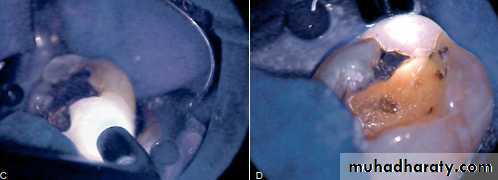

Test Cavity

The test cavity method for assessing pulp vitality is not rotinely used since, by definition, it is an invasive irreversible test. This method is used only when all other test methods are deemed impossible or the results of the other tests are inconclusive.

This is accomplished with a high-speed #1 or #2 round bur with proper air and water coolant. The patient is not anesthetized while this procedure is performed, and the patient is asked to respond if any painful sensation is felt during the drilling procedure. If the patient feels pain once the bur contacts sound dentin, the procedure is terminated and the class I cavity preparation is restored

If the patient fails to feel any sensation when the bur reaches the dentin, this is a good indication that the pulp is necrotic and root canal therapy is indicated.